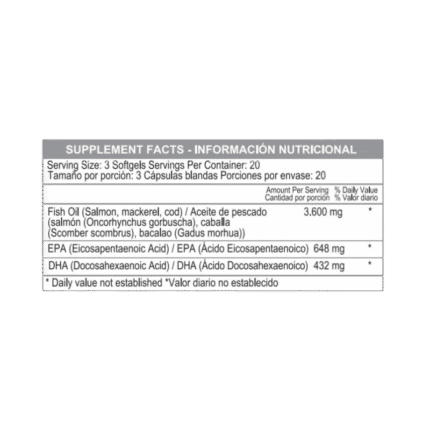

Potente mezcla de ácidos grasos esenciales Omega 3, 6 y 9 con 1200 mg por cápsula. Contribuye a la salud cardiovascular, cerebral y de la piel. Ideal para quienes buscan bienestar integral y nutrición completa en una sola cápsula diaria

El Triple Omega 369 es una combinación esencial de ácidos grasos que apoya funciones vitales del cuerpo. Esta fórmula proporciona los beneficios del Omega 3, 6 y 9, esenciales para mantener una buena salud.